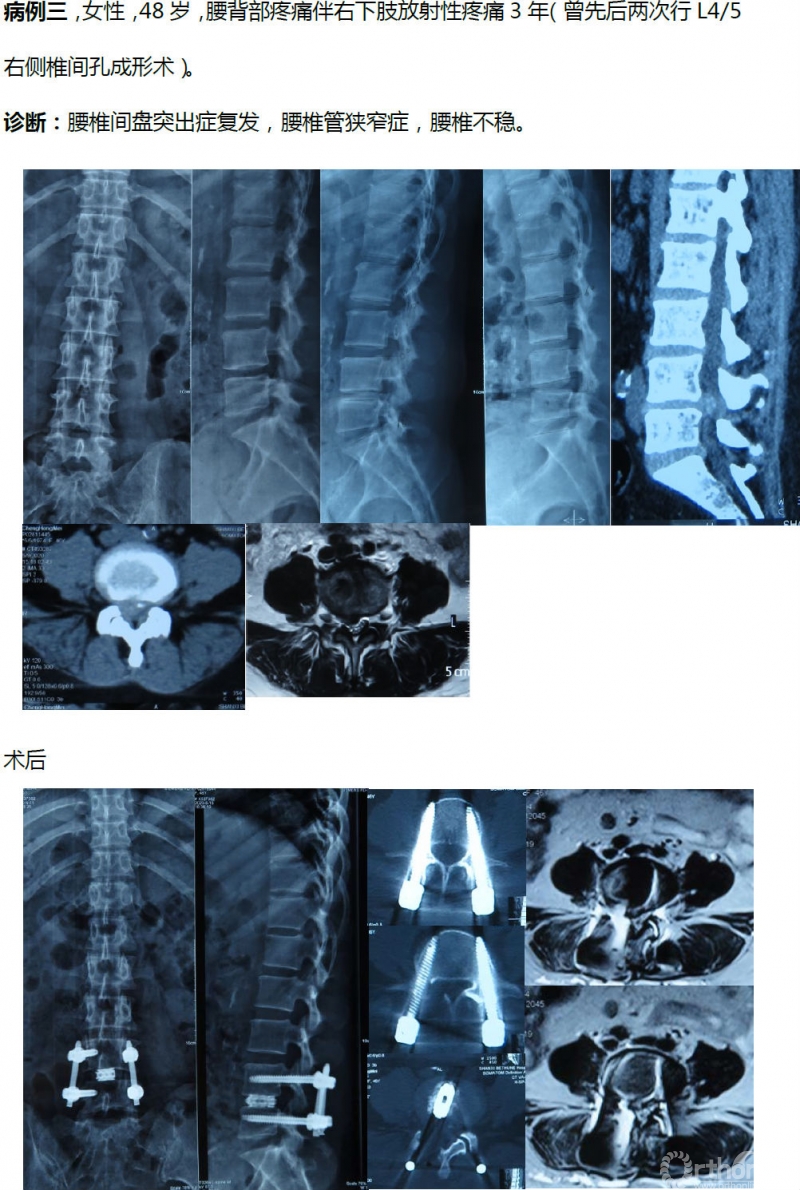

病例分享:(滑动查看)